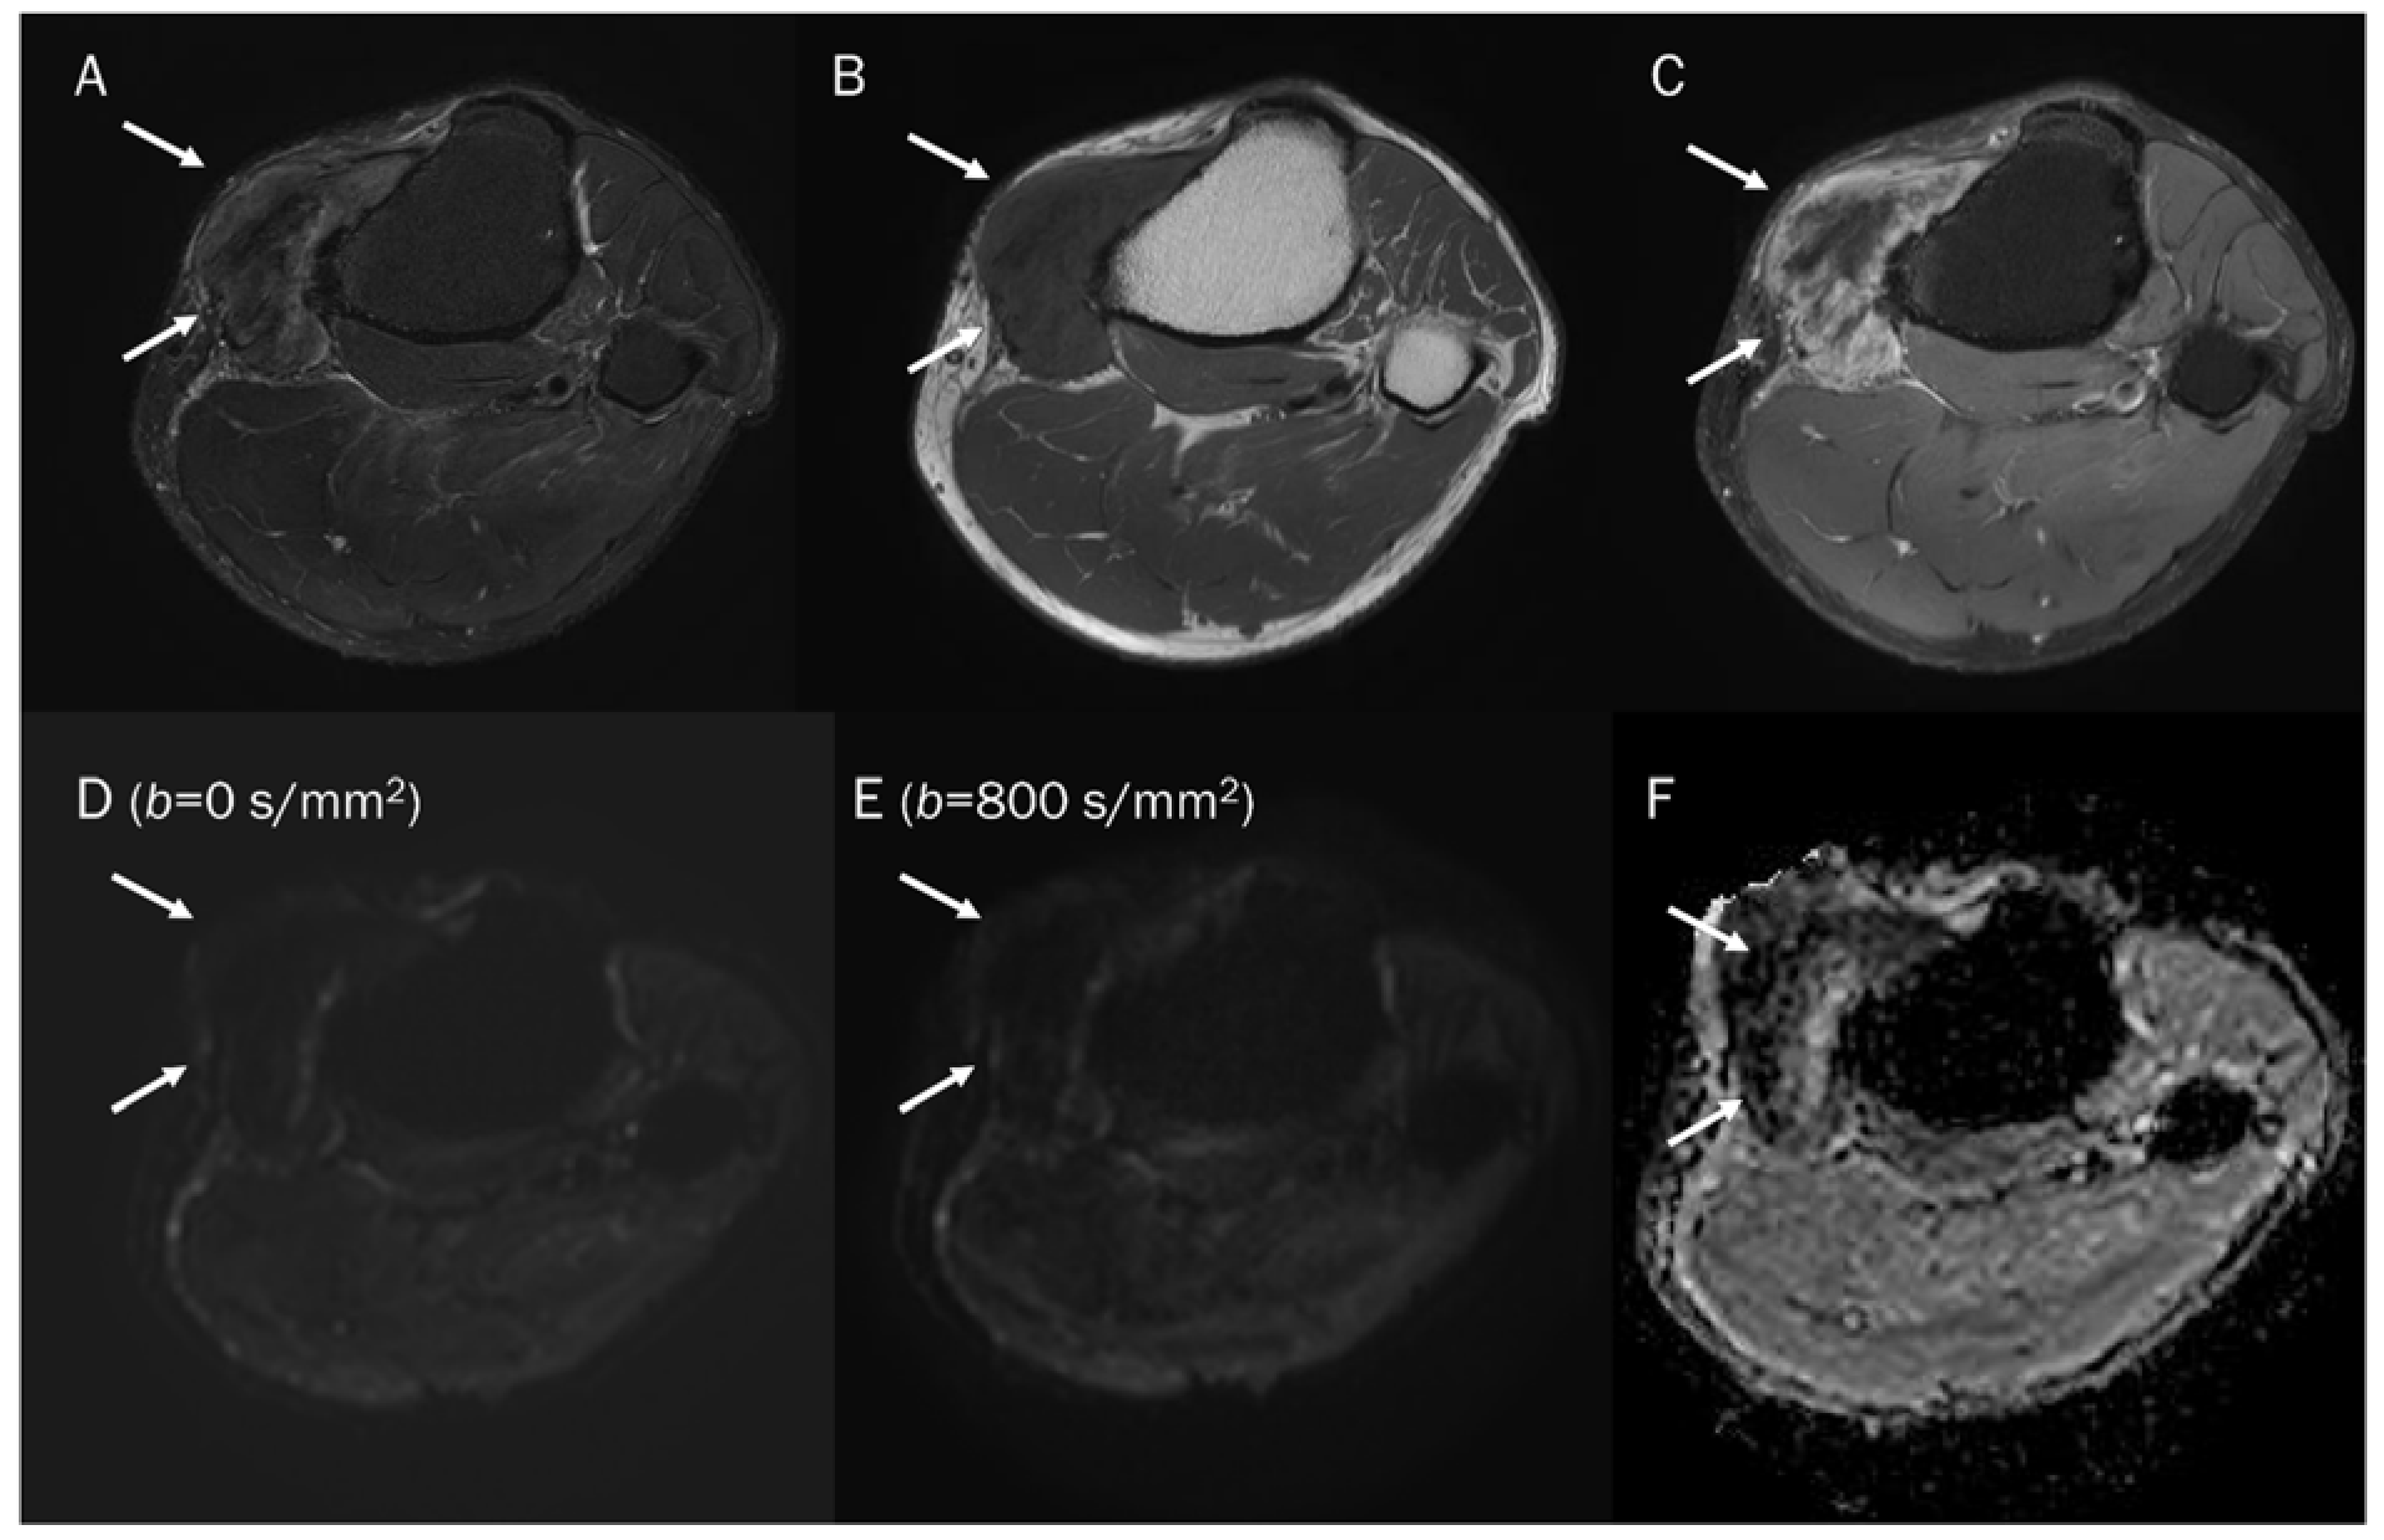

7.3. Benign Bone and Soft Tissue Tumors

| Lesions | Pitfalls | Content |

|---|---|---|

| Benign cyst | T2 shine-through | Free water |

| Hematoma | ||

| Acute stage | T2 black-out | Deoxyhemoglobin |

| Early subacute stage | T2 black-out | Intracellular methemoglobin |

| Chronic stage | T2 black-out | Hemosiderin |

| Benign tumors | ||

| Non-ossifying fibroma | T2 black-out | Collagen fibers |

| Giant-cell tumor | T2 black-out | Hemosiderin |

| Gouty tophi | T2 black-out | Monosodium urate crystal |

| Modic type 1 vertebral endplate change | T2 black-out | Lipid laden cells |